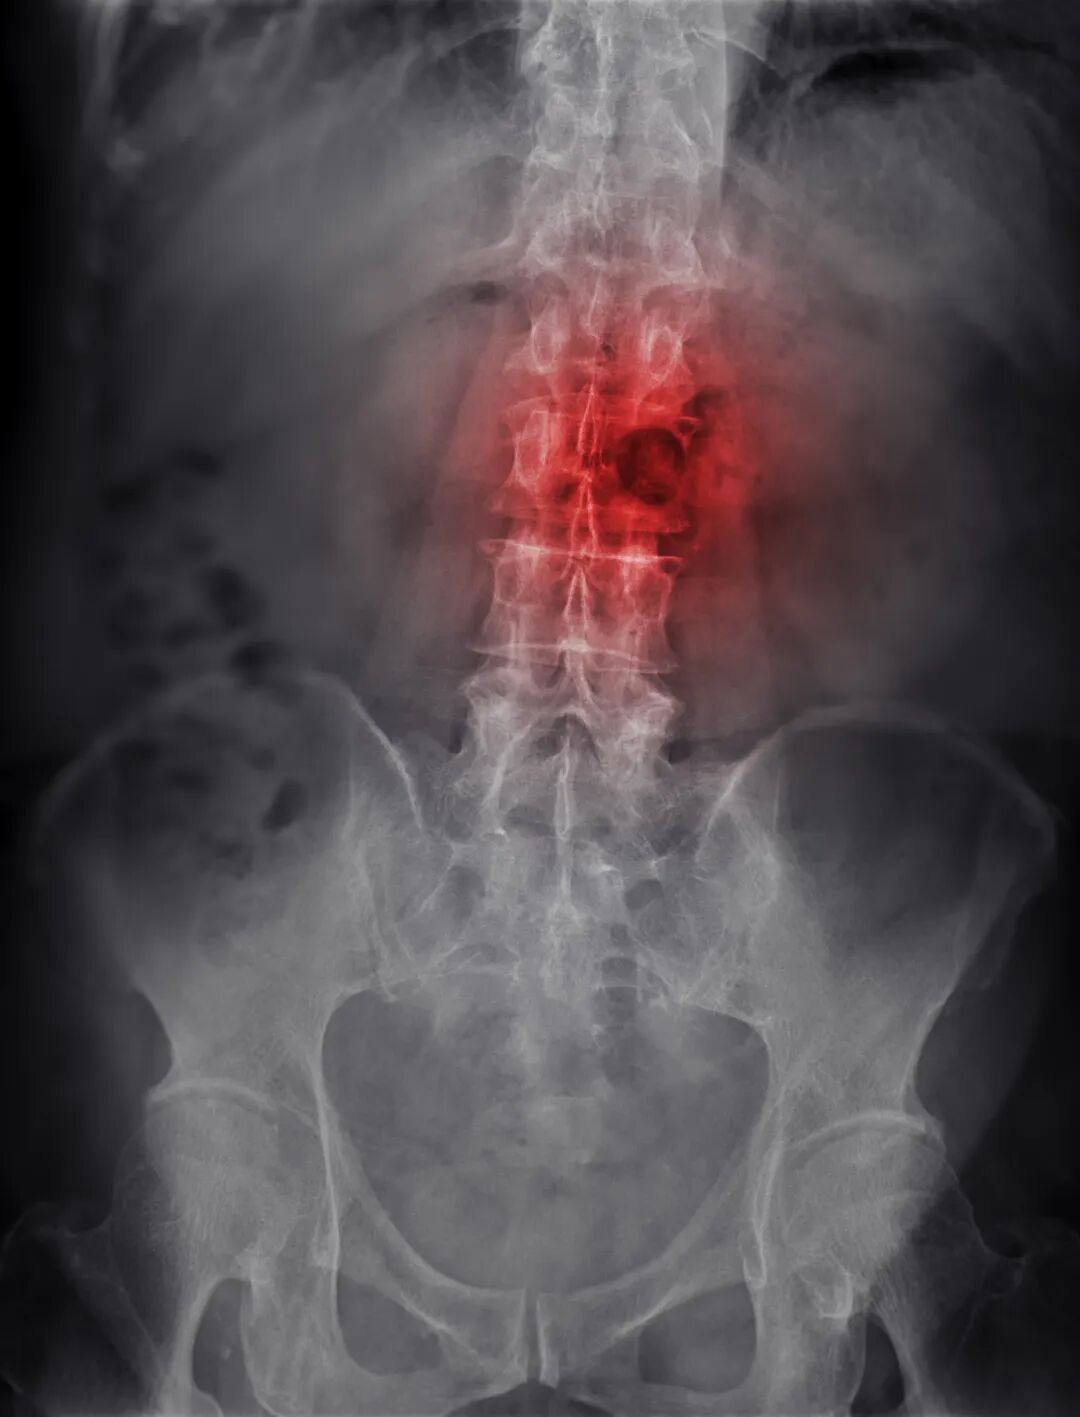

癌症骨转移不是悄无声息,3 种预警信号,早发现早干预!

对癌症患者而言,骨转移是令人担忧的并发症之一,但其发生并非毫无征兆。中医认为,骨为肾之府,骨转移多因正气亏虚、癌毒侵袭骨骼,导致肝肾不足、气血瘀滞。

若能及时捕捉这3种预警信号,尽早干预并配合中医调理,就能有效降低骨转移风险,守住康复防线。

3种骨转移预警信号,早发现早干预

这3种信号多与骨骼及周围组织受癌毒侵袭相关,需与普通劳损区分开:

1. 固定部位骨痛,夜间加重

不同于运动后的酸痛,骨转移预警痛多固定在脊柱、肋骨、四肢等部位,呈持续性钝痛或刺痛,夜间平躺时痛感会明显加剧,服用普通止痛药效果不佳。中医认为这是“癌毒瘀阻经络,气血不通则痛”的表现。